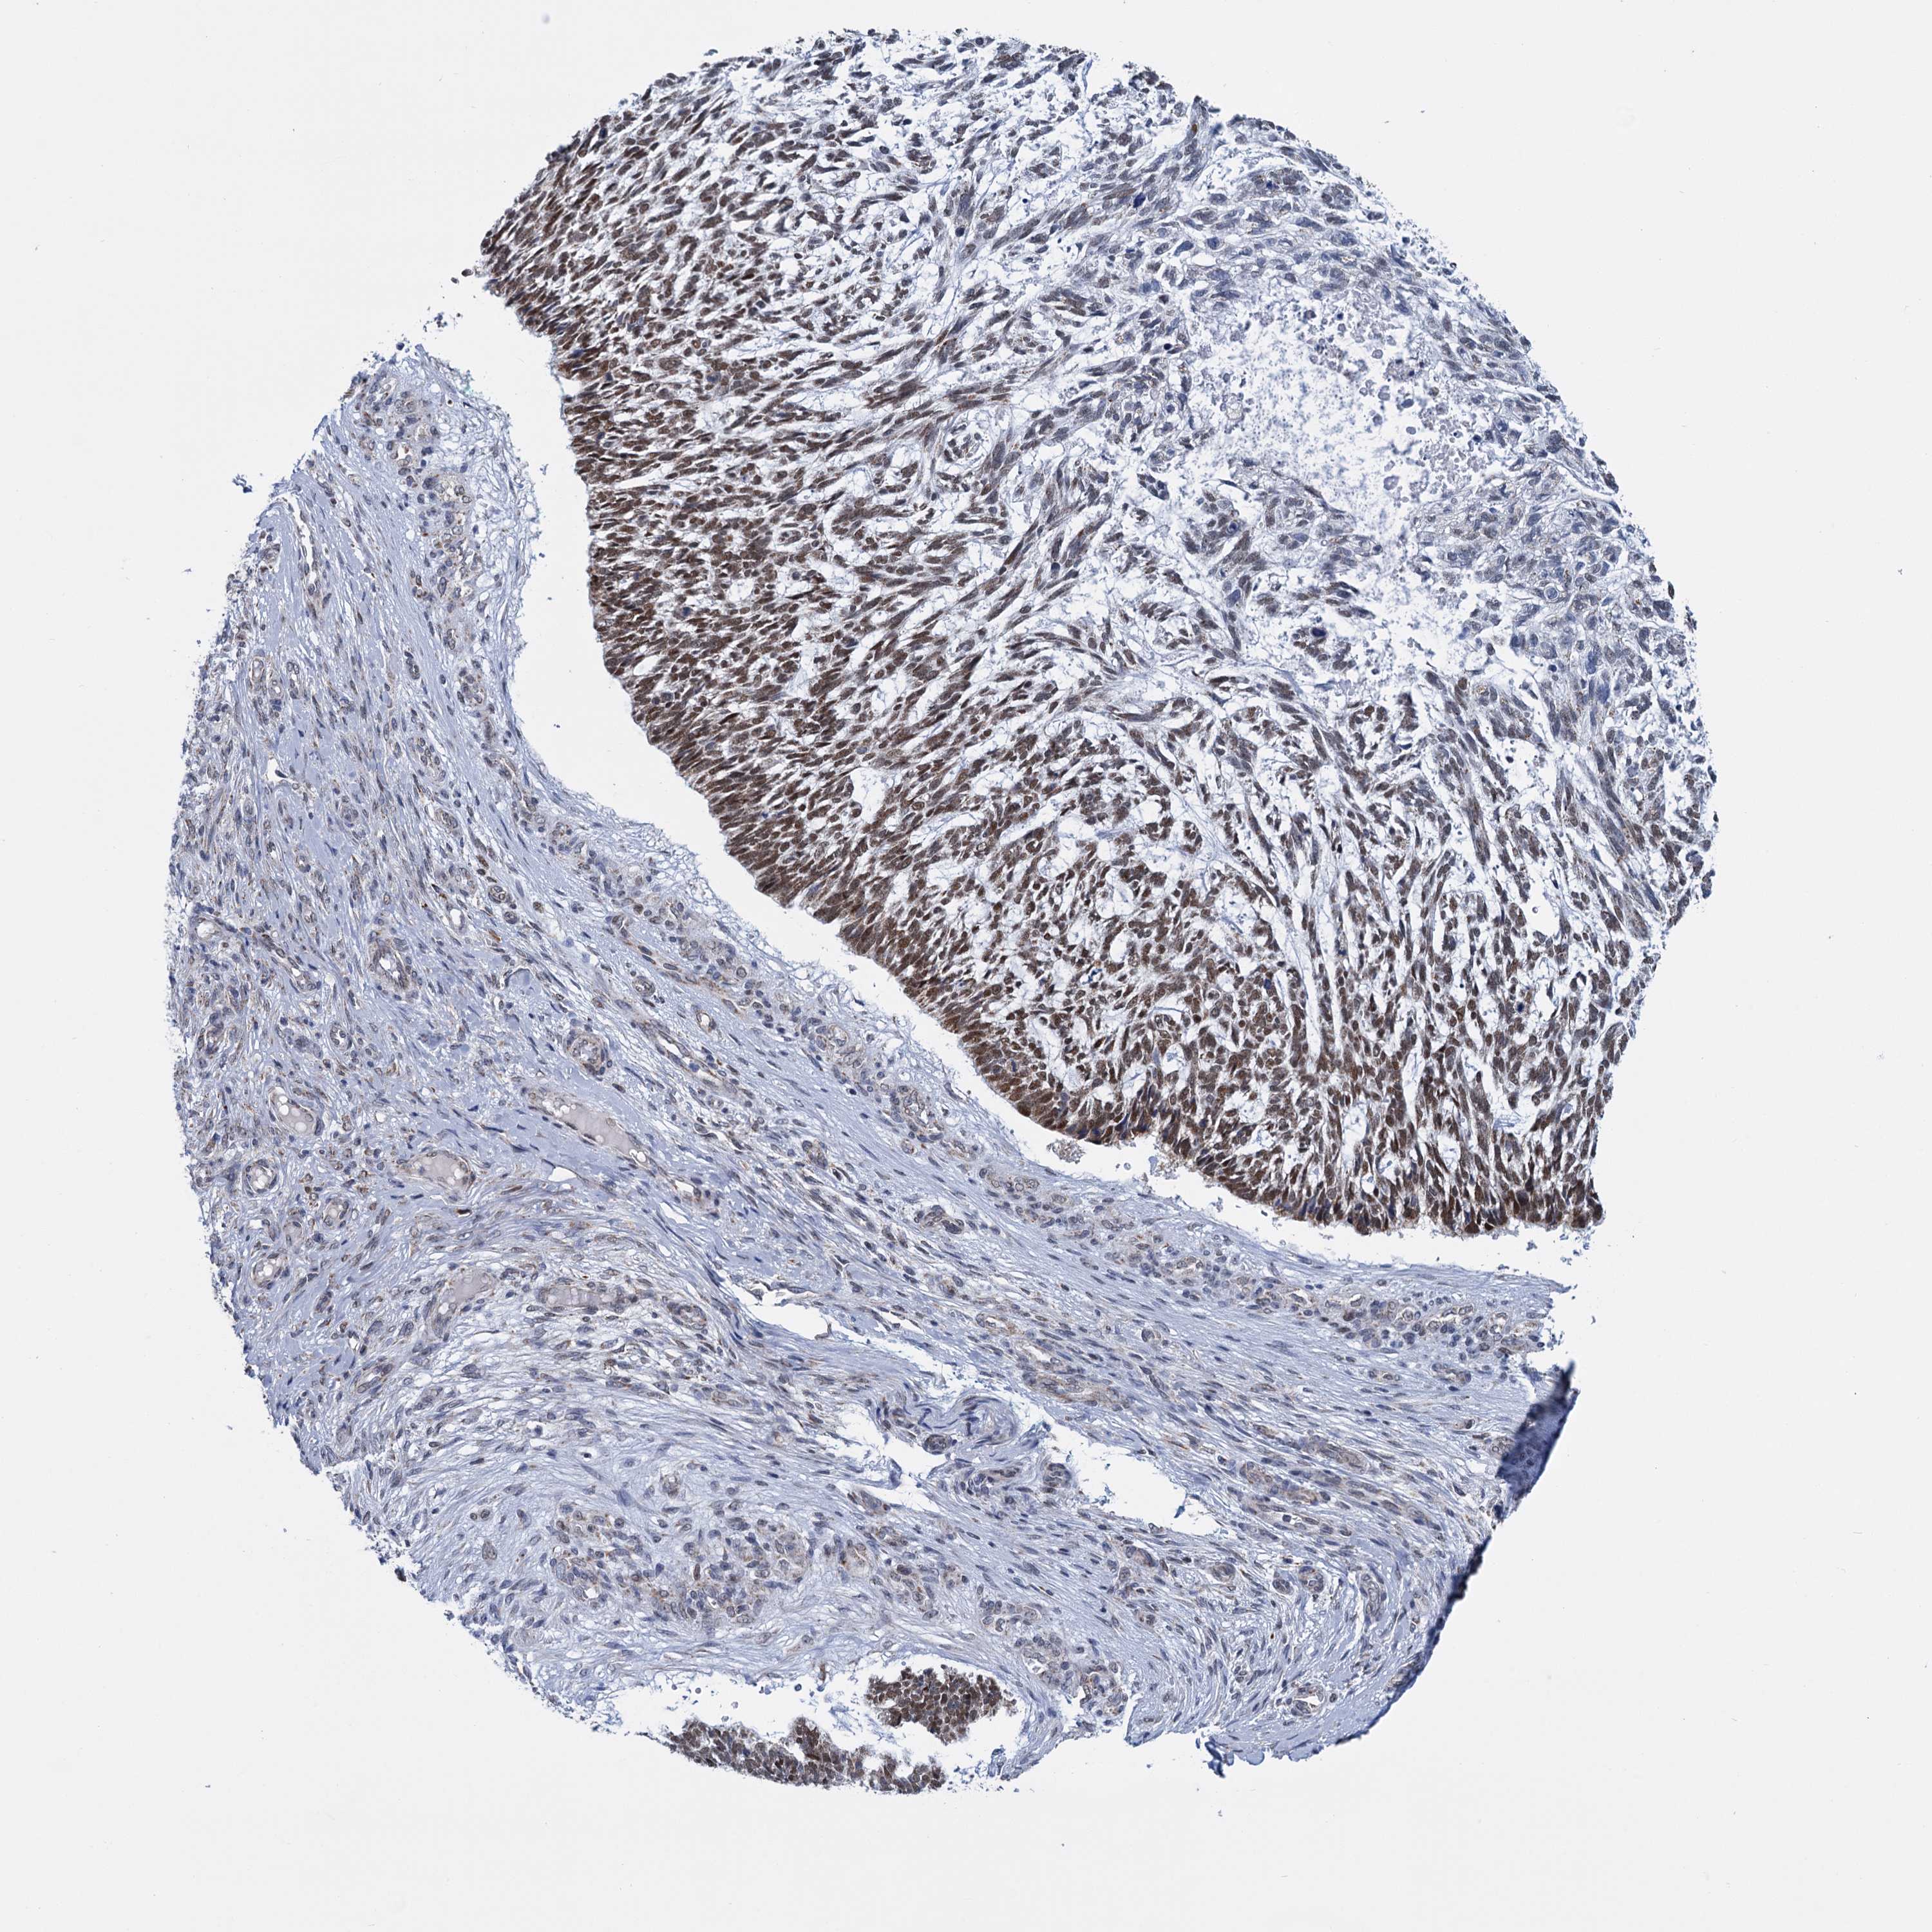

SKIN CANCER - Protein expressioni

A mouse-over function shows sample information and annotation data. Click on an image to view it in a full screen mode. Samples can be filtered based on level of antibody staining by selecting one or several of the following categories: high, medium, low and not detected. The assay and annotation is described here.

Antibody staining in the annotated cell types in the current human tissue is reported as not detected, low, medium, or high, based on conventional immunohistochemistry profiling in selected tissues. This score is based on the combination of the staining intensity and fraction of stained cells.

Each image is clickable and will lead to virtual microscopy that enables deeper exploration of all samples and also displays staining intensity scores, fraction scores and subcellular localization as well as patient and tissue information for each sample.

Antibody HPA038710

Staining

Medium

Intensity

Moderate

Quantity

75%-25%

Location

Nuclear

Squamous cell carcinoma, NOS

Squamous cell carcinoma, metastatic, NOS